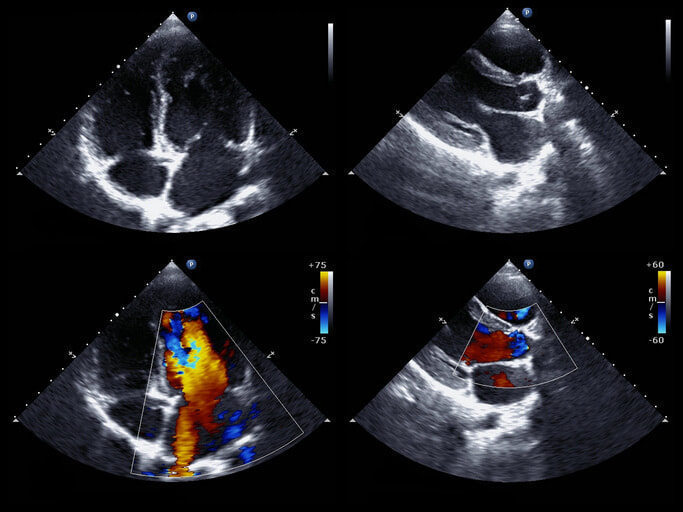

• 心臓超音波検査:心臓の動きや弁膜症の有無などをチェックします。